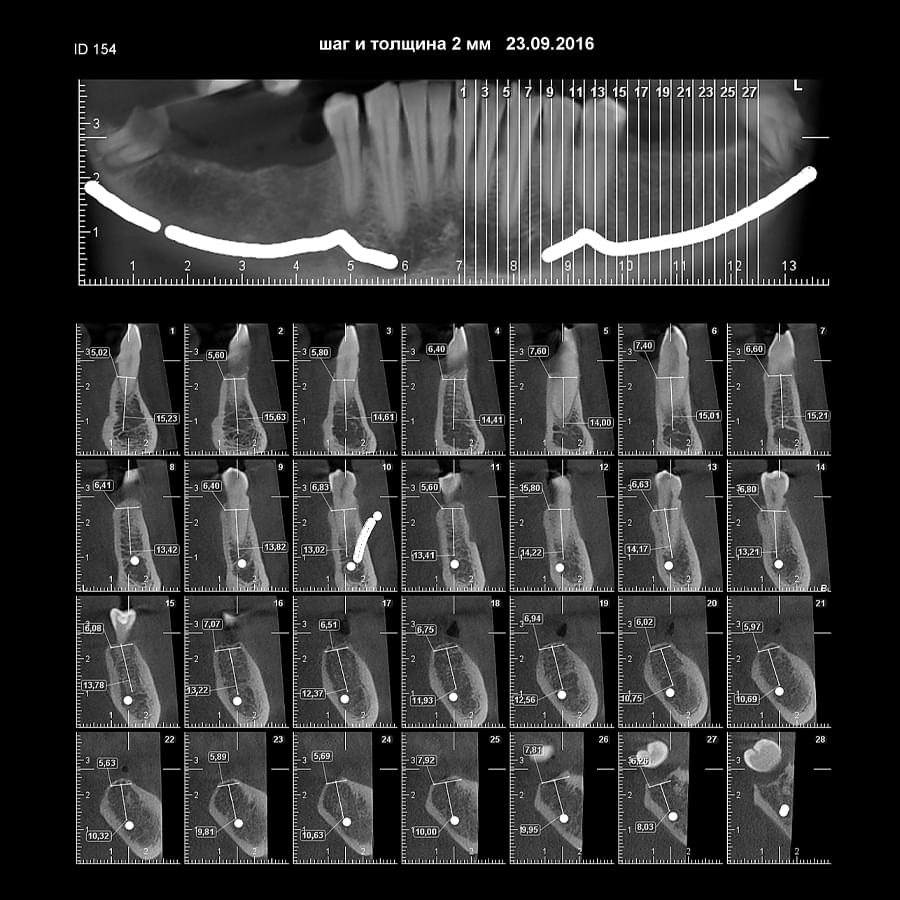

Мережа діагностичних центрів "МАЙРЕЙ ЛАБ" забезпечує точну та надійну діагностику

щелепно-лицевої ділянки з мінімальним ризиком для пацієнтів.

Ми використовуємо найсучасніше обладнання відомого виробника PLANMECA, що дозволяє отримувати високоякісні зображення за короткий час. Крім того, ми маємо власний сервер, на якому створюємо окрему скриньку для кожного лікаря, що забезпечує максимальну зручність та ефективність роботи.

Наша команда має великий досвід у діагностиці що дозволяють проводити точну діагностику

та вчасне виявлення проблем.